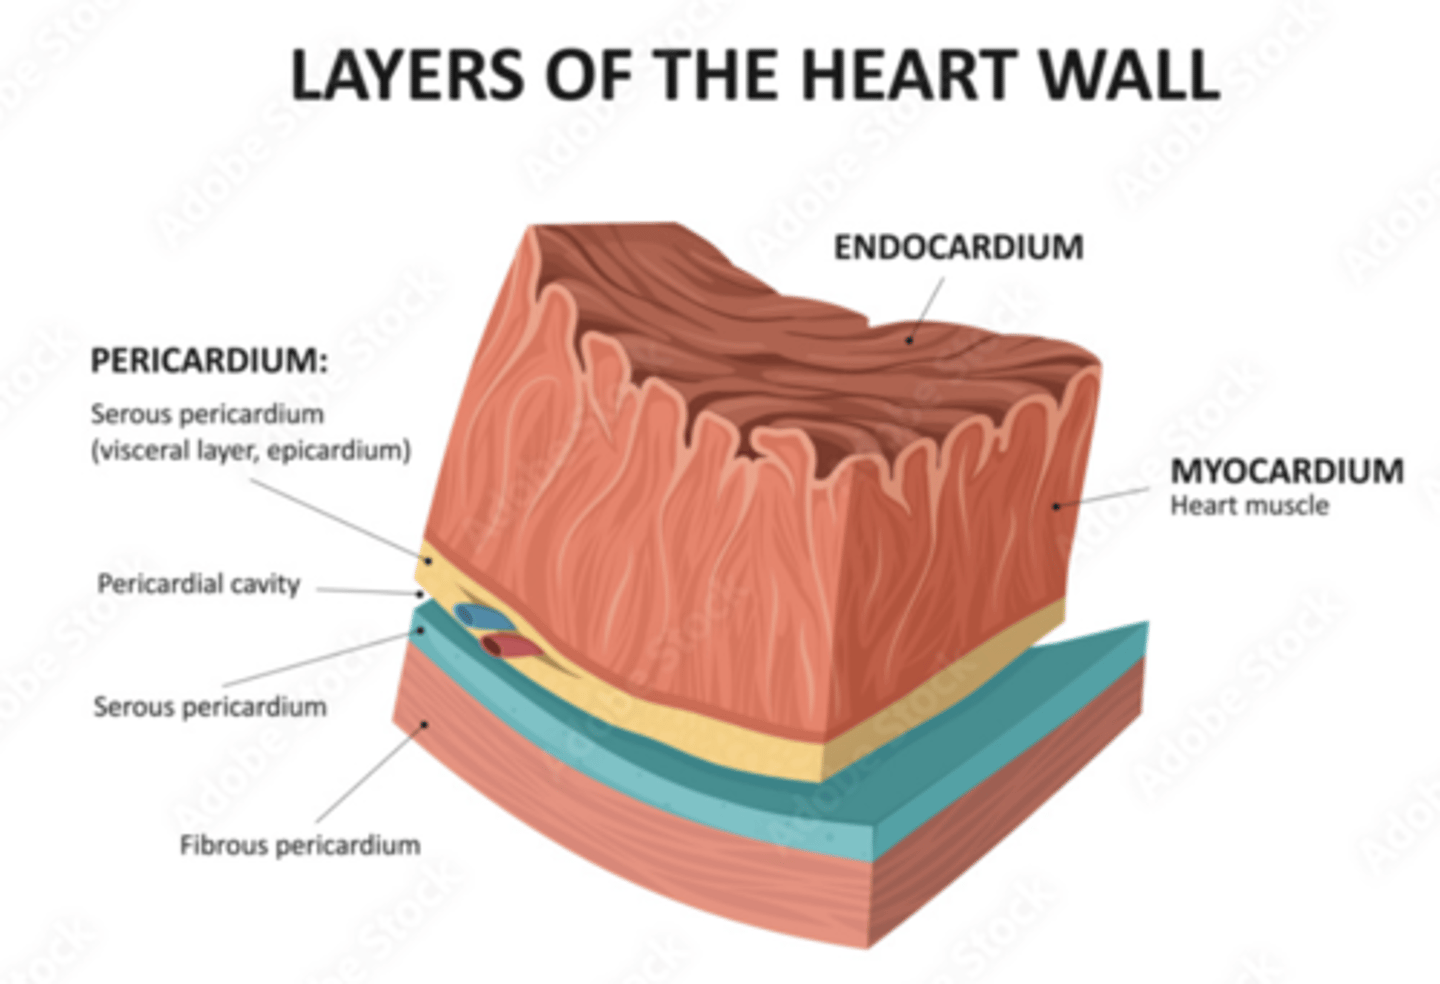

What are the layers of the pericardium?

The pericardium consists of two main layers:

- the fibrous pericardium

- the serous pericardium

How is divided the serous pericardium?

. Visceral layer or Epicardium (innermost). Adheres to the heart

. Parietal layer (outermost)

Between these layers is the pericardial fluid (pericardium cavity )

What is the fibrous pericardium?

the tough, outer layer

protects the heart

maintains its position in the thorax.

defines the boundaries of the medium mediastinum

What are the layers of the heart?

Epicardium: outermost covering.

Myocardium (right << left)

Endocardium or endothelium: inner thin layer of simple squamous epithelium